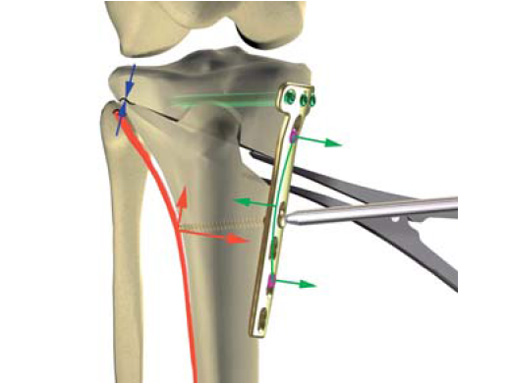

The correction is planned on a long-leg standing x-ray. After surgery, the mechanical axis should pass through a point 63% on the lateral side of the total width of the tibial plateau in the frontal plane. A transverse or slightly oblique incision is used to avoid damage to the saphenous nerve. The distal fibers of the medial collateral ligament are detached from the tibia. Under fluoroscopic control, two wires are placed in the proximal tibia marking the transverse osteotomy plane. The cut usually starts at the upper margin of the pes anserinus and ends at the tip of the fibula on the lateral side. The wires are placed exactly parallel to the tibial plateau thus taking into consideration the individual tibial slope of the patient. An incomplete cut of the posterior two-thirds of the proximal tibia is performed with an oscillating saw guided by the wires. Continuous irrigation avoids burn injury to the bone. A second osteotomy is now performed in the anterior third of the tibia in an angle of 100 ending above the patellar tendon insertion. A smaller saw blade is used and the complete anterior cortex is cut exactly in the frontal plane. The osteotomy is now gradually opened by inserting flat chisels or a spreader-chisel into the posterior osteotomy cleft. This process may take some minutes and can usually be completed without fracture of the lateral cortex. A bone spreader is now placed in the posteromedial edge of the tibia and the chisels are removed. The leg is extended and the correction is checked with the fluoroscope. A long metal rod is placed between center of the hip joint and center of the ankle joint. The projection of this rod should be at the planned point of correction on the tibial plateau lateral of the midline. Eccentric collapse of the medial joint space may cause accidental overcorrection. In this case pressure on the foot may simulate loading and body weight. The correction can be fine-tuned by opening or closing the spreader. The TomoFix Medial Tibia Plate is now placed in a subcutaneous pocket. The implant is precontoured and usually fits well to the bone surface. The distance holders avoid compression of the medial collateral ligament and the pes anserinus. Three proximal bolts are placed near the subchondral sclerosis zone. The position of the bolts is adapted to the anatomy of the proximal tibia giving optimum purchase for the bolts. An oblique lag screw is inserted distal to the osteotomy. This screw in the first combination hole allows careful compression of the lateral osteotomy hinge and pretensioning of the implant. A stab incision is created on the shaft and the implant is fixed monocortically with bolts. The lag screw and the distance holders are replaced by bolts. The medial collateral ligament is released longitudinally to reduce medial compartment pressure and the wound is closed in layers. An overflow drain may be used. Clinical and experimental work has proven that when this technique is closely followed, corrections up to and over 15 mm can be performed without bone grafting or use of bone substitutes.